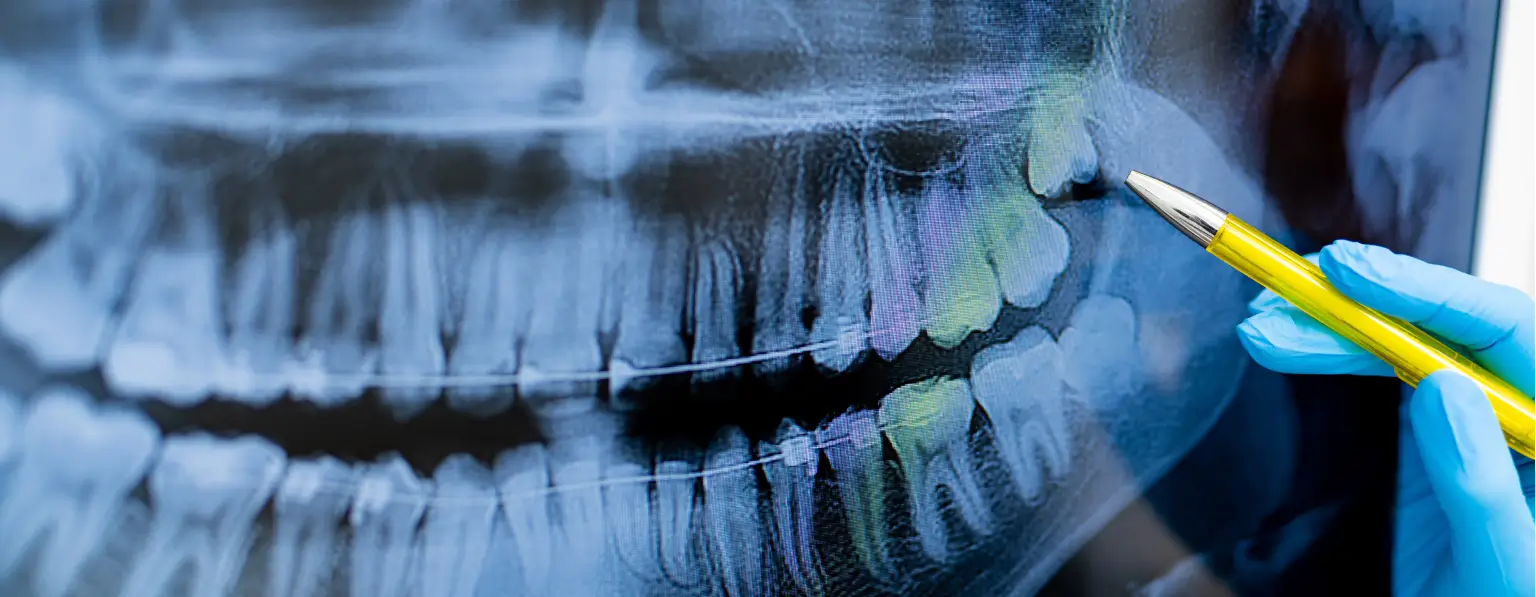

Digital Xrays

At Family Dentistry Complete, we are always making efforts to make our dental services as comfortable and as convenient as possible for the clients. Dr. Francis as one of the reputed and trusted dentists has the best equipment in his dental office. We use digital X-ray at our facility because we know that it is convenient, safer for you and it is more efficient when compared to the traditional X-rays.

Safer X-ray Option

No need to be worried or concerned about being exposed to harmful radiation every time you need to get an X-ray as part of your dental procedure. Dr. Francis ensures you get the very best in dental healthcare services.

Environmentally Friendly X-ray

By using dental care facilities that use environmentally friendly equipment, you are also doing your part in protecting and handing over a safer environment to the subsequent generations while at the same time ensuring safer healthcare options for yourself.

Convenient

Instead of the bitewing, you will be using a more comfortable digital sensor. The digital sensor when placed in your mouth will capture clearer images with much less radiation, which can be viewed instantly in a computer.

These are just some of the advantages of using digital X-rays in dental practices. Family Dentistry Complete ensures that you enjoy the best dental healthcare services.

Faster and Efficient

You need not have to drive back several miles to collect your X-rays. Your X-rays can even be emailed to you, which you can review anytime, and from anywhere you like. Digital X-ray allows your dentist to act fast because they will be able to review your X-rays immediately. Digital X-rays by minimizing the waiting period speeds up the treatment process.